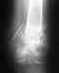

Пожалуйста, ответьте! У подруги ( -она сама врач!) в родах 2 недели назад разрыв сифиза 3 ст.-3 см. Консультации у травматологов противоречивые. Операция под вопросом. Какова врачебная тактика в таких случаях? Какова срочность операции. Сейчас ей рекомендован постельный режим и бандаж.И все.

Женщине 32 года, астеничного телосложения, индекс Соловьева не более 14см.Таз сужен 1 ст в прямом размере ( от крестца до лона) Ребенок первый. крупный - около 4 кг, окружность головы новорожденного 38см. Травма произошла в начале потуг, был хруст, боли не было, невозможно было поднять ноги в положении лежа. Родила естесственным путем.